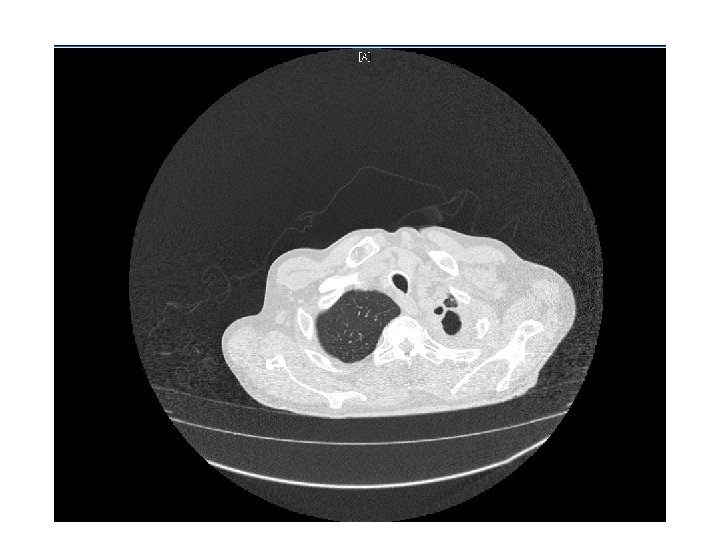

CT Chest • Multiple cavitary lesions • Largest left lung apex 3. 8 x 4. 7 cm with nodular thickened wall • Smaller cavitary lesions in L lung base • R lung: smaller areas of ground-glass opacities with areas of tree in bud appearance.